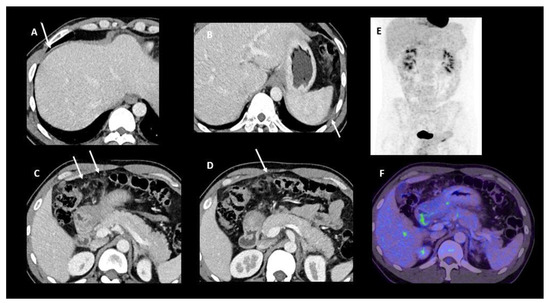

2.3. Positron Emission Tomography (PET)-CT

2.4. Imaging Combination